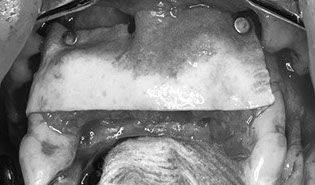

This regenerative course focuses on barrier membrane particulate bone grafts. The volume of bone and related procedures covered in this course is for appositional augmentation. The game changing Versah bone drilling system is demonstrated to treat ridges effectively and avoid the need for grafting in the correct circumstances. Bone grafting materials – alloplasts, allografts and the use of autologous blood draws for Autologous Stem Cell Harvest and manufacture of advanced platelet rich fibrin (A-PRF), injectable platelet rich fibrin (i-PRF) and the use of fibrin glue. Advanced surgical techniques of tissue release (Soft Brushing) and advanced surgical site closure techniques are presented in detail along with bone physiology and metabolism. Indications for extraction and immediate implant insertion, esthetic complication of implant position and angulation are also covered in detail.

Recognise and perform the necessary hard tissue site preparation and securing of the membrane prior to l graft placement

Perform the procedures of site preparation to membrane fixation, autologous bone harvesting, layered graft placement and suture closure

in pig’s head laboratory